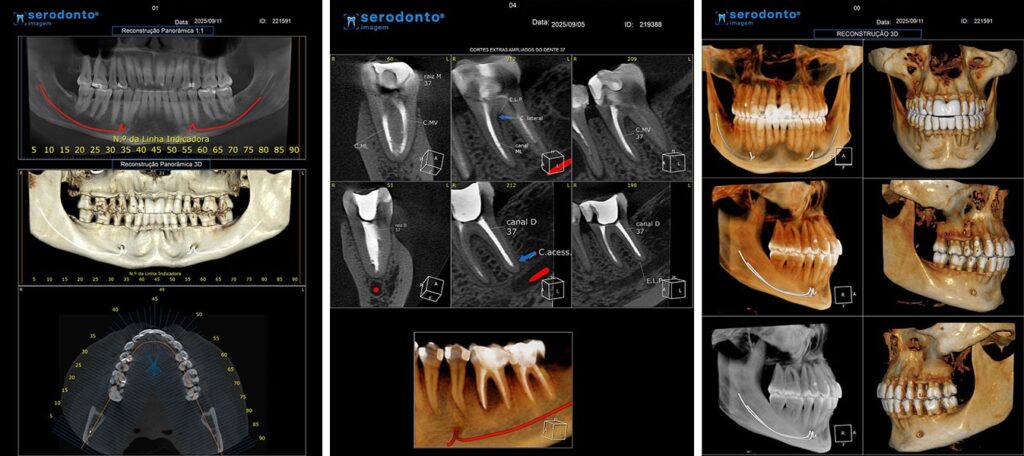

A tomografia de feixe cônico (Cone Beam) oferece imagens tridimensionais detalhadas, essenciais para diagnósticos precisos e planejamento de tratamentos complexos.

Avaliação precisa de estruturas ósseas e dentárias.

Planejamento para implantes dentários e cirurgias.

Identificação de anomalias anatômicas.

Imagem em alta resolução e tridimensional.